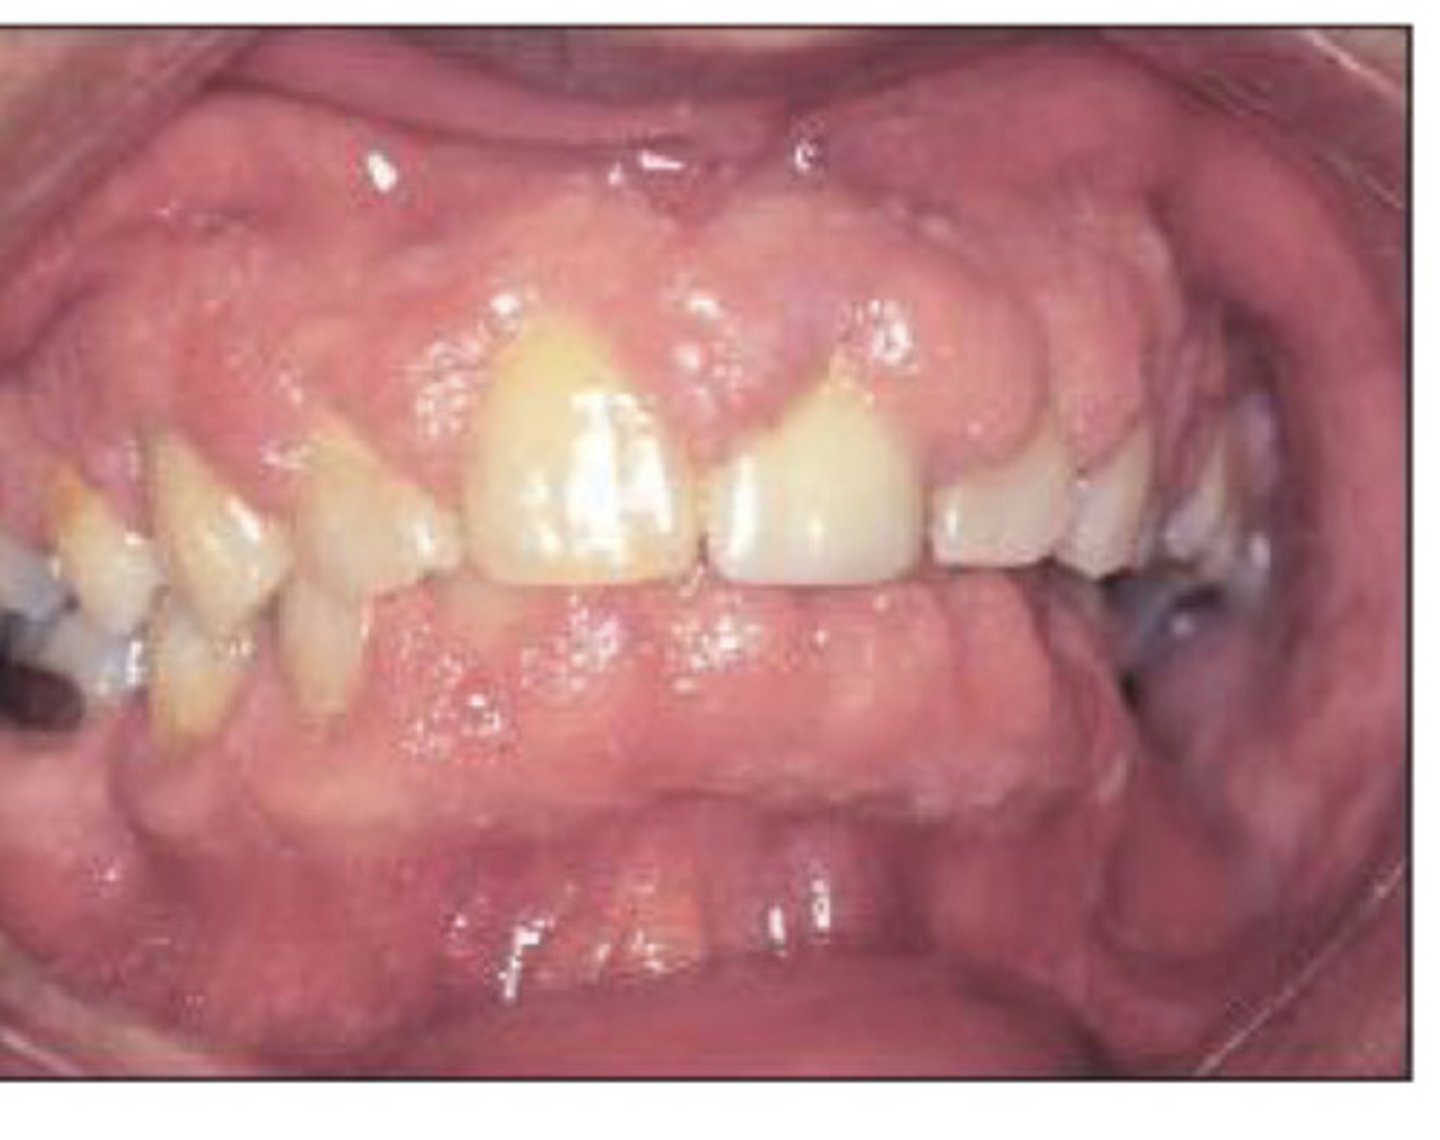

Drug induced gingival hyperplasia

What is this?